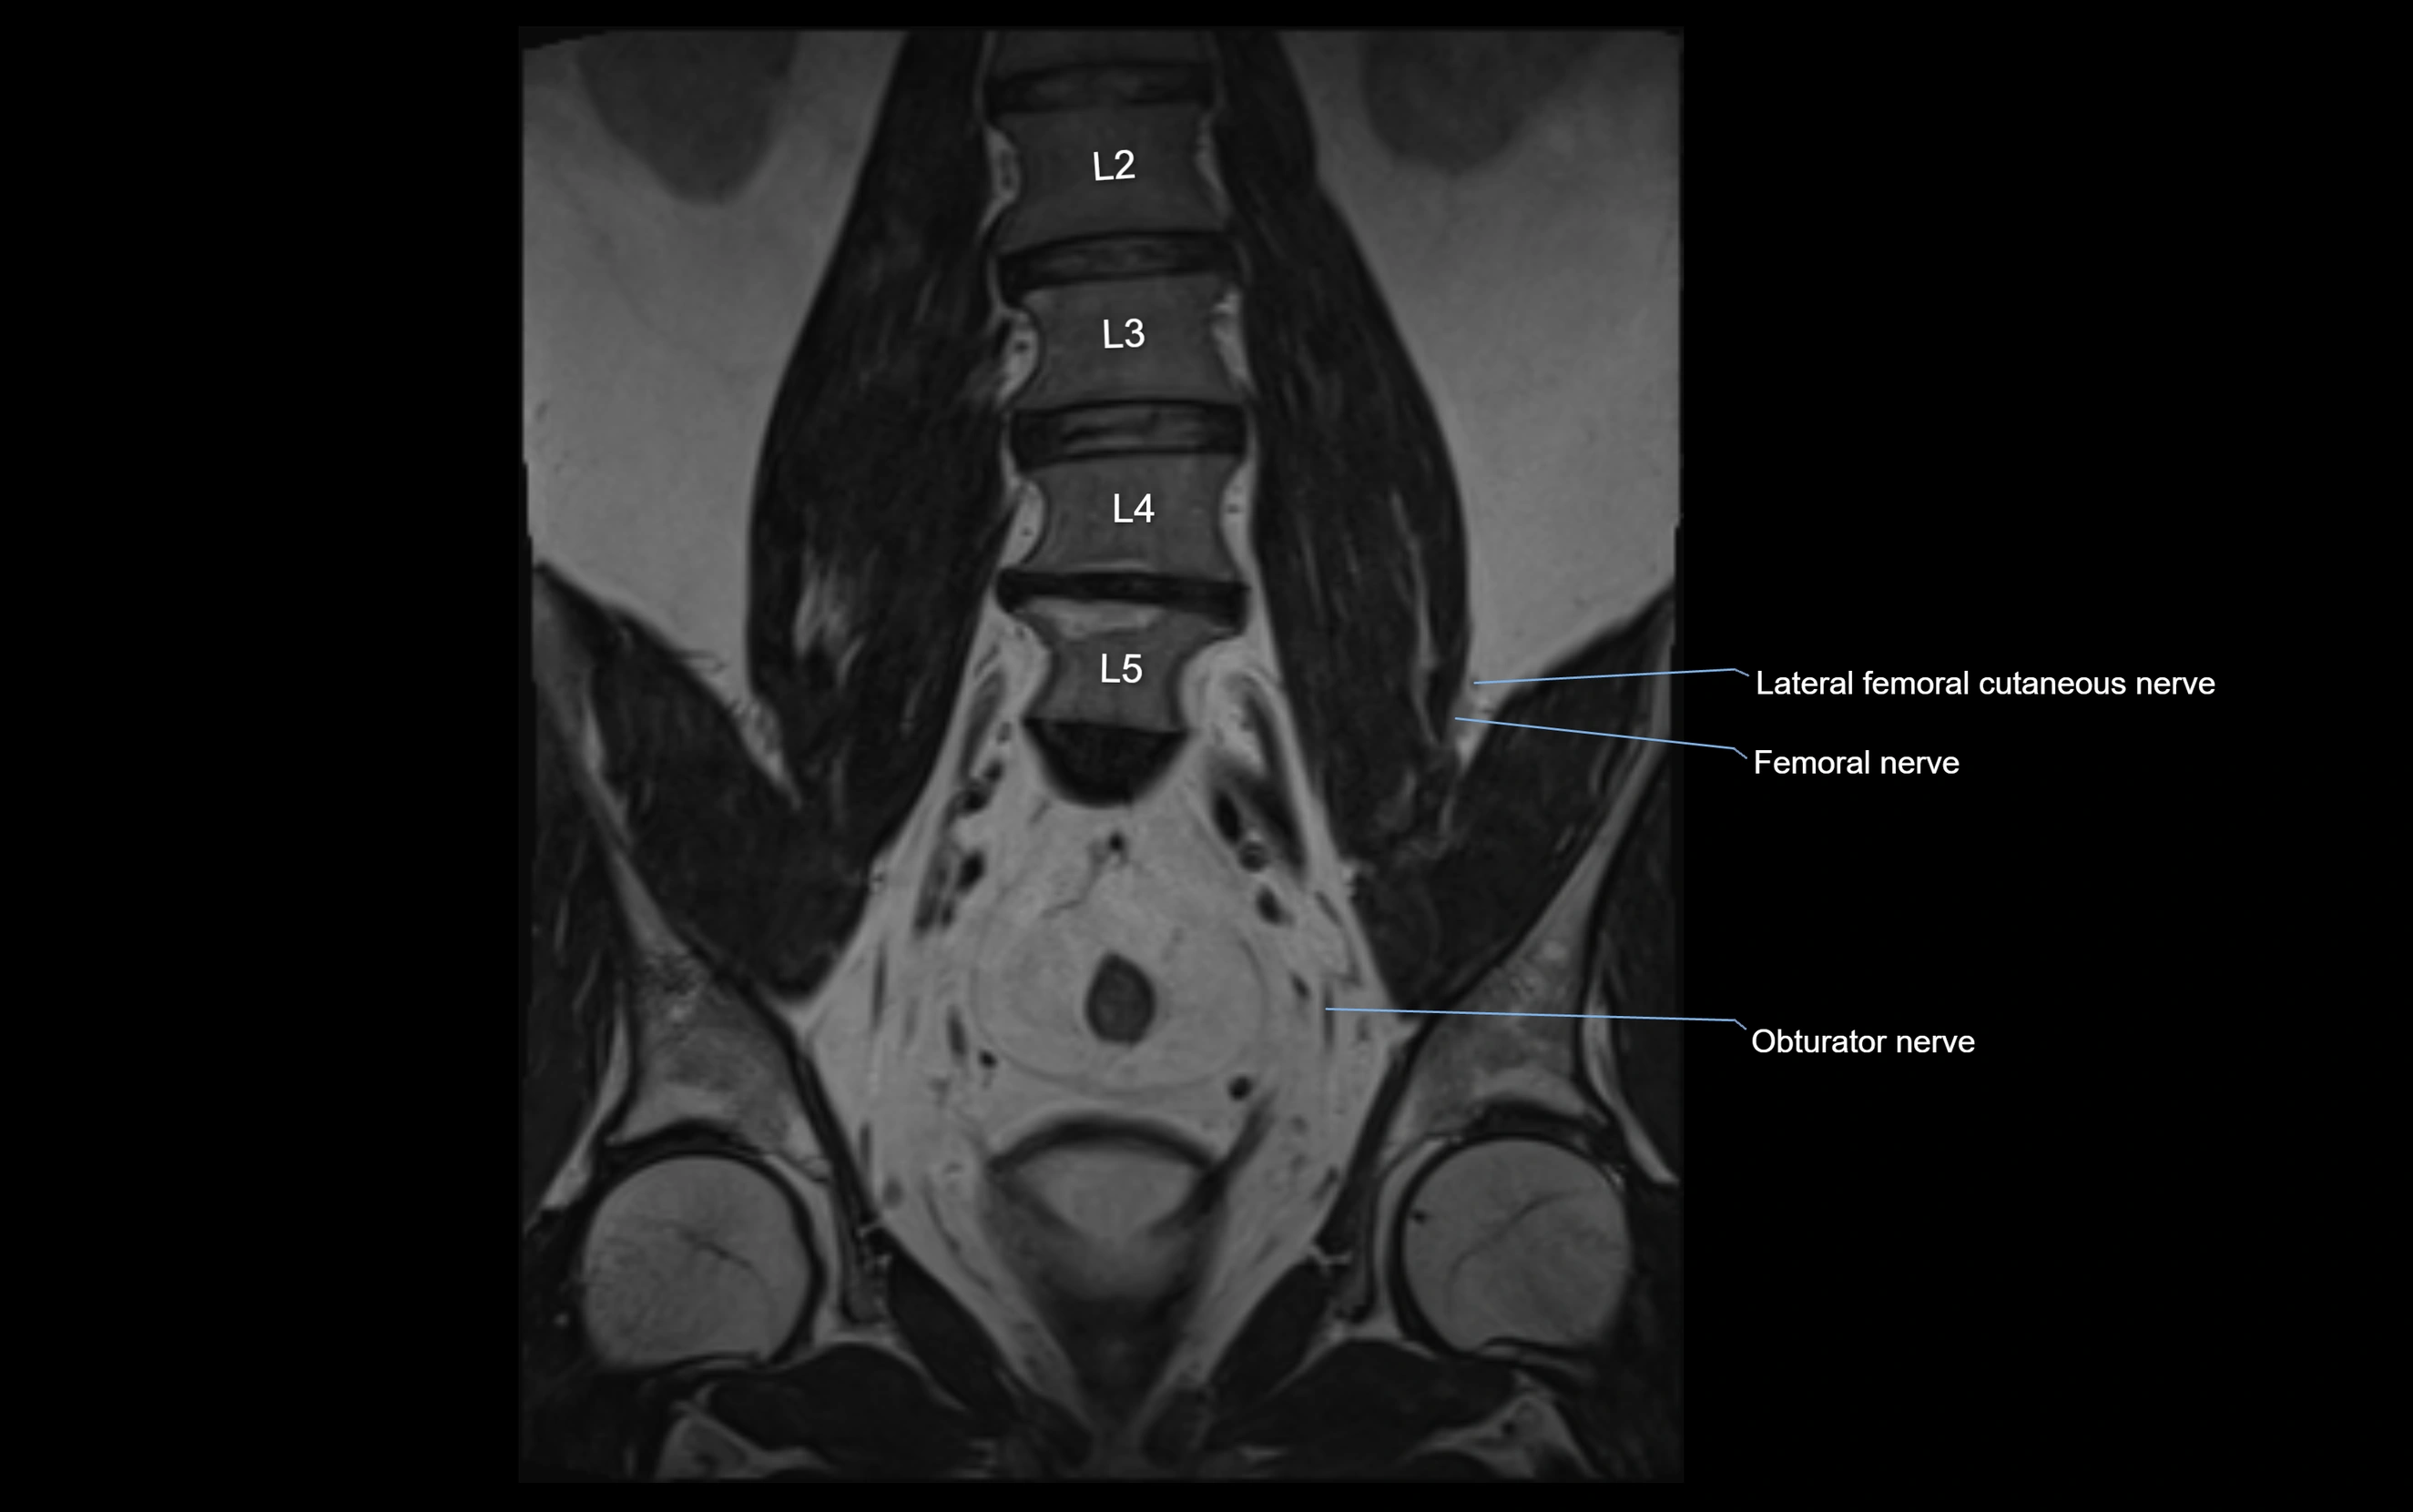

MRI image

image